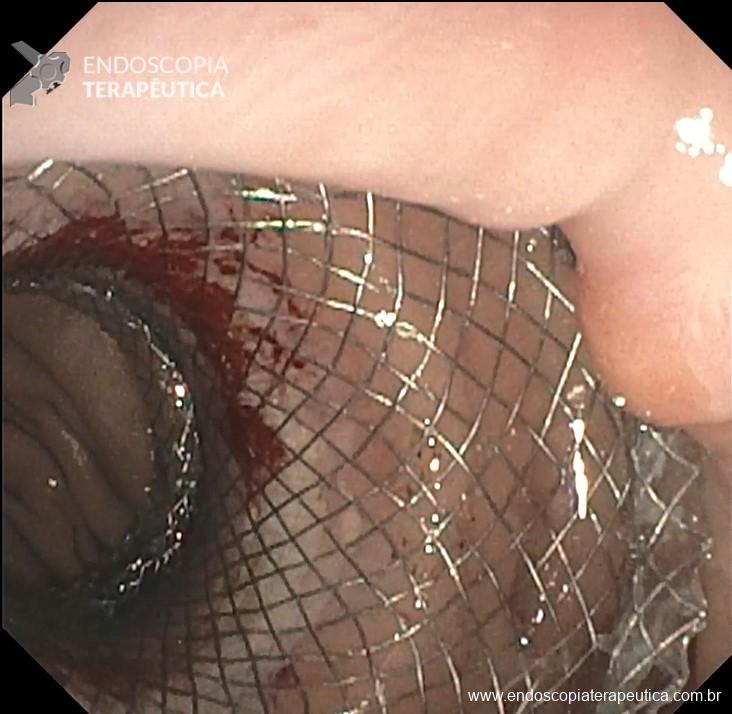

Passo 3: Dilatação do LAMS e procedimento

- Em duas etapas: aguardar maturar a fístula em 1 a 2 semanas e seguir com procedimento após esse período com a prótese metálica já expandida ou dilatação do LAMS logo após disparo;

- Etapa única: realizar dilatação logo após passagem da LAMS. Há opção de fixação da prótese com over-ther-scope-clip (Padlock e Ovesco) ou endossutura (Apollo) para minimizar a migração;

Dilatação da LAMS com balão hidrostático até 20 mm de diâmetro, com confirmação da dilatação por visão endoscópica e fluoroscópica (Figura 7 e 8);

- Prosseguir com o tratamento endoscópico proposto: CPRE principalmente

- Dicas: em uso de duodenoscópios ou ecoendoscópios, entrar com aparelho em paralelo com a prótese; a prótese é móvel, então a fluoroscopia ajuda no posicionamento e minimiza a fricção com a prótese, evitando migração (Figura 9).